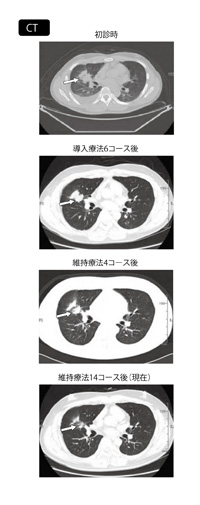

初診時に認められた病巣部(矢印)が導入療法6コース後には縮小傾向を示し、維持療法14コース後は、かなり小さくなっている

患者さんと相談しながら中止時期を決めているが、維持療法開始後2年以上経っても良好な状態を保っている患者さんもいる(画像4)。